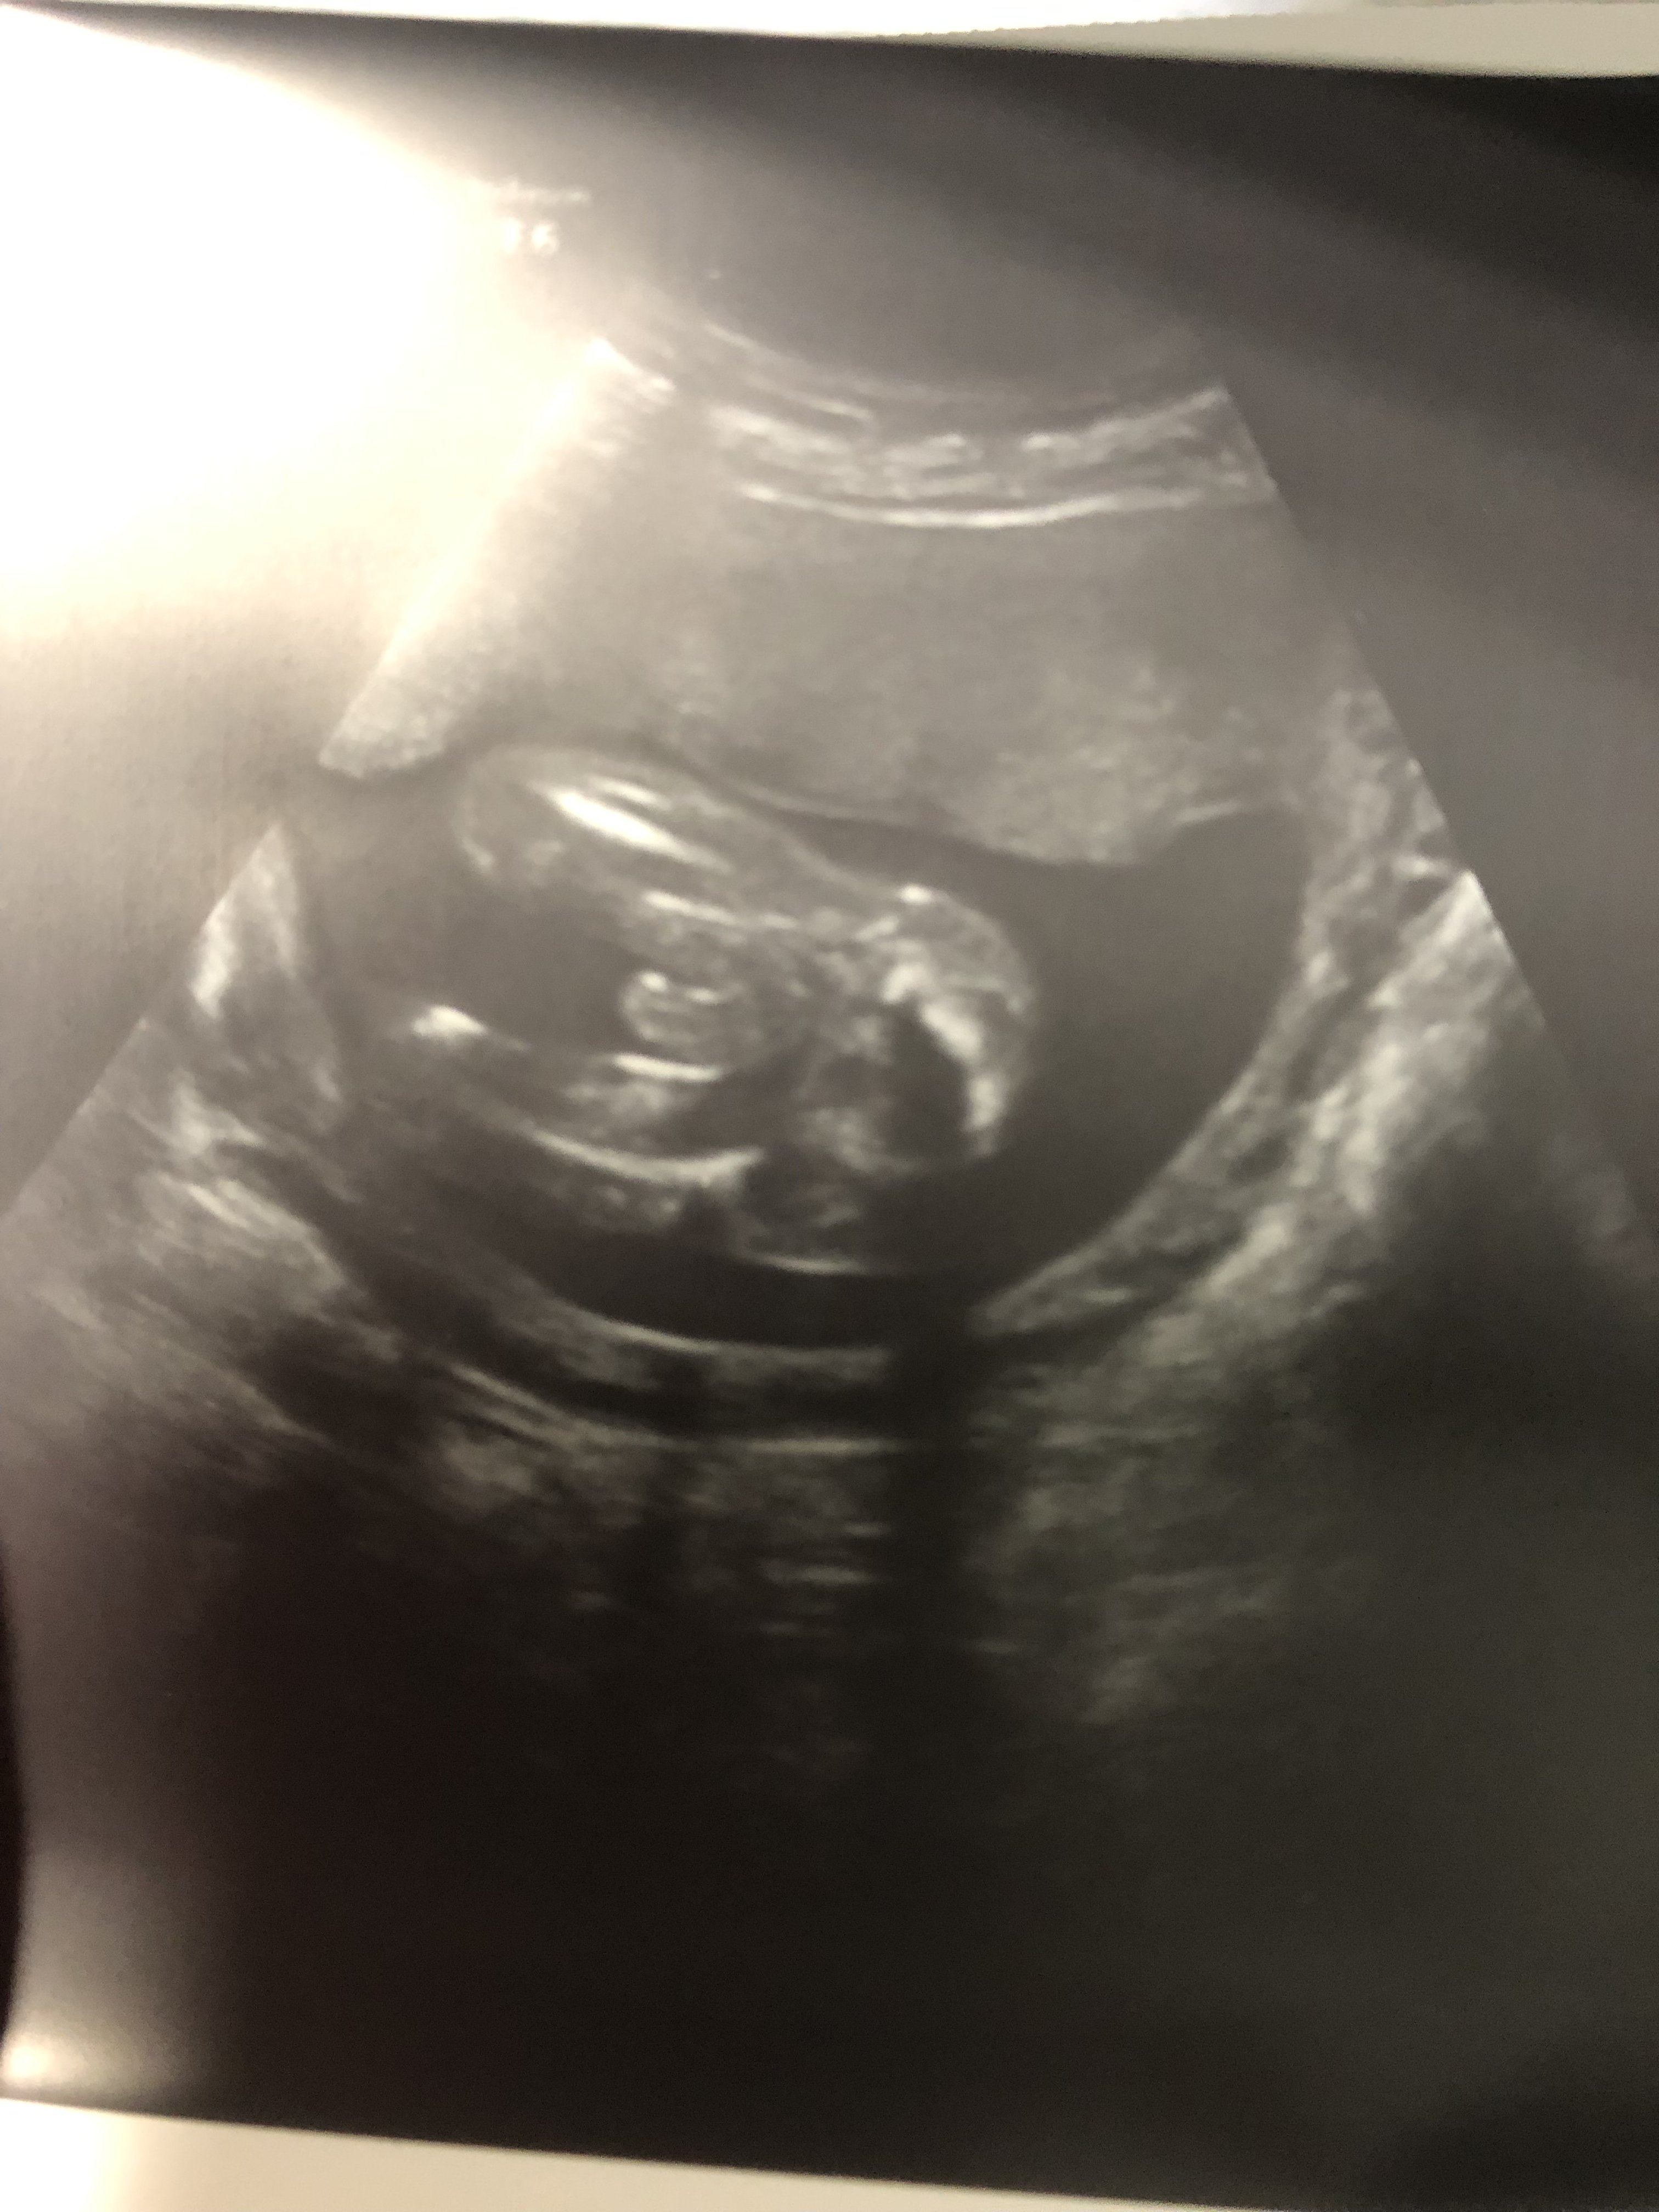

Usg chłopak czy dziewczynka

Witam w 19 tygodniu ciąży dowiedziałam się ze będę miała dziewczynkę w 20 tyg okazało się jednak , że to chłopak. Sama już nie wiem bo na jednym usg widać na pewno dziewuche a na drugim chłopca. Może to pempowina ?? Może ktoś mi pomoże rozwiązać ta zagadkę